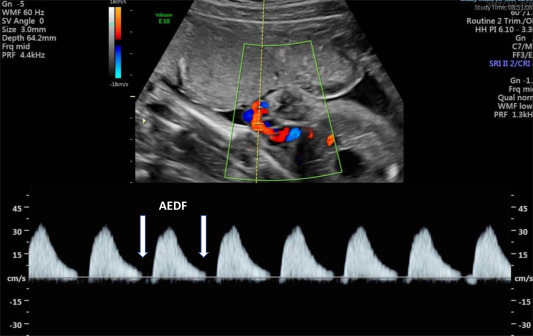

Color Doppler Obstetric Scan

Color Doppler Obstetric Scan is an advanced ultrasound technique used during pregnancy to assess the blood flow within the placenta, umbilical cord, and fetal blood vessels. By combining traditional ultrasound imaging with Doppler technology, which measures the speed and direction of blood flow, this scan provides valuable information about the vascular health of the placenta and fetus. It can help detect conditions such as placental insufficiency, fetal growth restriction, or abnormalities in umbilical cord blood flow, which may impact fetal well-being and pregnancy outcomes. Additionally, Color Doppler Obstetric Scan is utilized to monitor conditions like preeclampsia and to guide management decisions, ensuring optimal care for both the mother and the developing fetus throughout pregnancy.